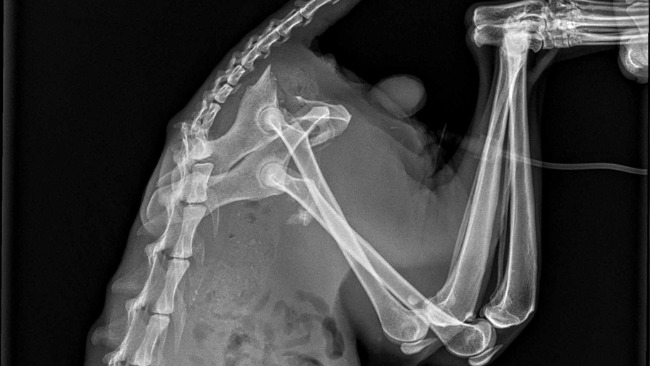

Od tygodni jeździmy z nim codziennie do weterynarza. I od tygodni obserwujemy, jak Desperado desperacko chce żyć. Nie może chodzić z powodu strzaskanej miednicy. Nie można było zdecydować się na operację, dopóki stan ogólny kota na to nie pozwalał.

A przed nim najważniejsza operacja: poskładania kości miednicy i nóg w całość. Operacja odbędzie się w całodobowej klinice. Operował naszego kota będzie doktor Krajewski. Wierzymy, że się uda i że w końcu Desperado stanie na nogi.